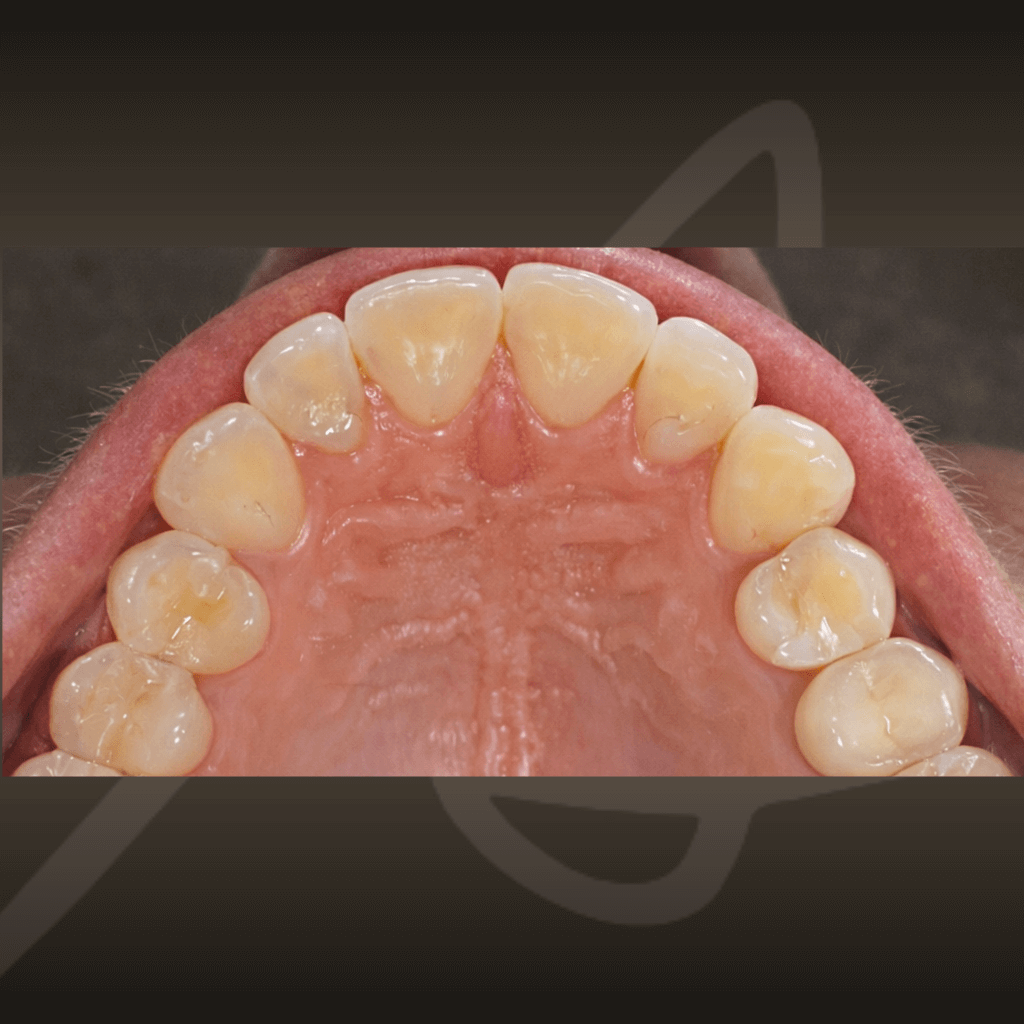

Ортодонтията не е само въпрос на подредба. Правилното лечение подобрява захапката, речта и създава стабилна основа за дългосрочно дентално здраве. Независимо от възрастта, ортодонтското лечение може да допринесе за по-добър функционален баланс и по-лесна поддръжка на зъбите във времето.